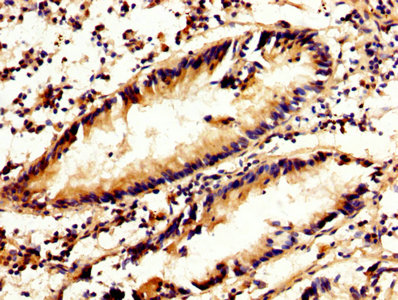

DescriptionCAPN2 Polyclonal Antibody. Unconjugated. Raised in: Rabbit.

ApplicationELISA, WB, IHC, IF, IP; Recommended dilution: WB:1:1000-1:5000, IHC:1:200-1:500, IF:1:50-1:200, IP:1:200-1:2000